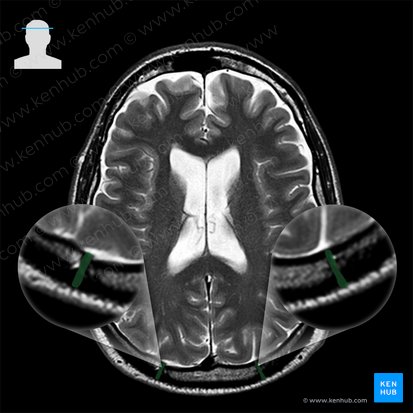

The lambdoid suture is the serrated interlocking joint between the two parietal bones and the occipital bone of the skull, whose name derives from its resemblance to the Greek uppercase letter lambda (Λ). It is one of the prominent sutures of the skull, easily identifiable on the posterior and lateral aspects. It is a fibrous (suture) joint, that has no movement (synarthrosis).

It extends between the two asterion on either side of the skull. The sagittal suture typically connects to the midpoint of the lambdoid suture at apex of the occipital bone, forming the lambda, which resembles the lowercase Greek letter lambda (λ). This point marks the location of the posterior fontanelle in the developing skull. Small bones called sutural (Wormian) bones are most commonly formed within the lambdoid suture.